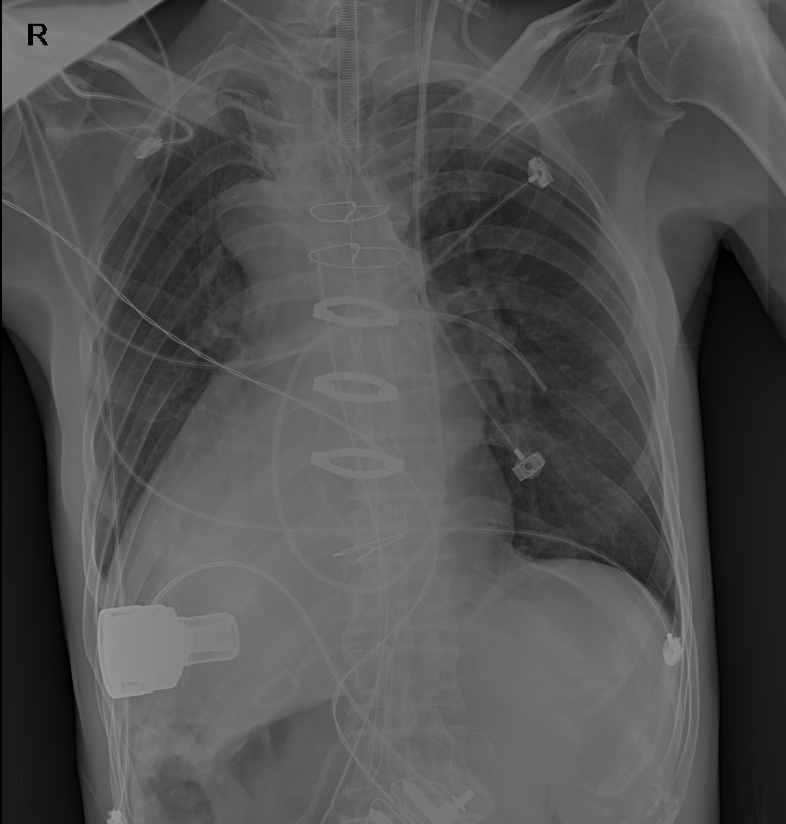

患者术后DR胸片

患者隗某,男性,71岁,因间断胸闷气喘3年余,加重1周于外院就诊效果不佳,慕名向心脏大血管外科张大发主任求医。经详细诊断,该患者因心脏瓣膜病导致终末期心力衰竭,心功能评估为Ⅳ级。患者为内脏左右反位的“镜面人”,心脏、肝脏、脾脏、胆囊等体内器官左右反位,位置如同正常器官的镜中像,使手术难度大幅增加。为此,心脏大血管外科会同超声医学科、医学影像科、心血管内科、重症医学科、呼吸与重症医学科、麻醉科、输血科、手术室等科室进行MDT会诊,组织术前讨论和评估,为该患者制定了科学的手术及后续诊疗方案。

经充分准备,张大发主任团队成功为患者实施左心室辅助装置植入术,术中手术医师凭借精湛技艺,“反其道而行之”进行操作,手术过程顺利,装置安全植入。随后,患者转入重症医学科二病区,术后第二天拔除气管插管,血流动力学平稳,生命体征恢复良好。目前,该患者转回心脏大血管外科普通病房,进行术后康复治疗。